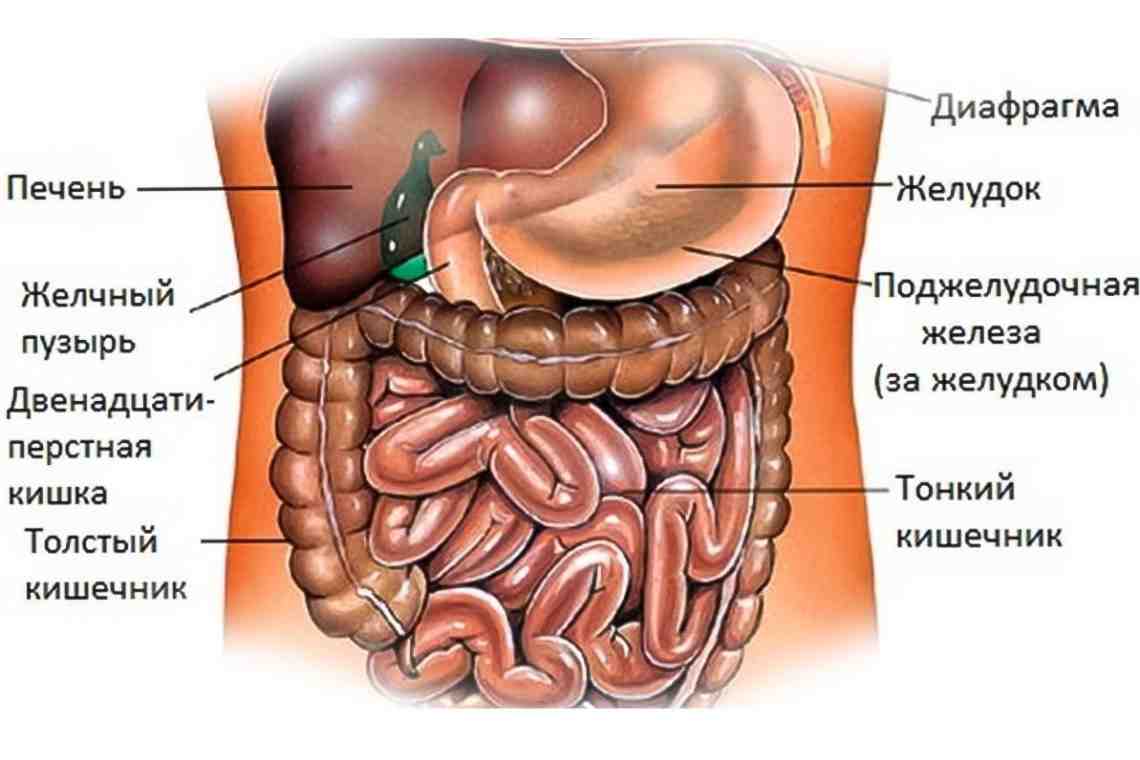

Анатомия желудка и сердца: визуализация и изучение